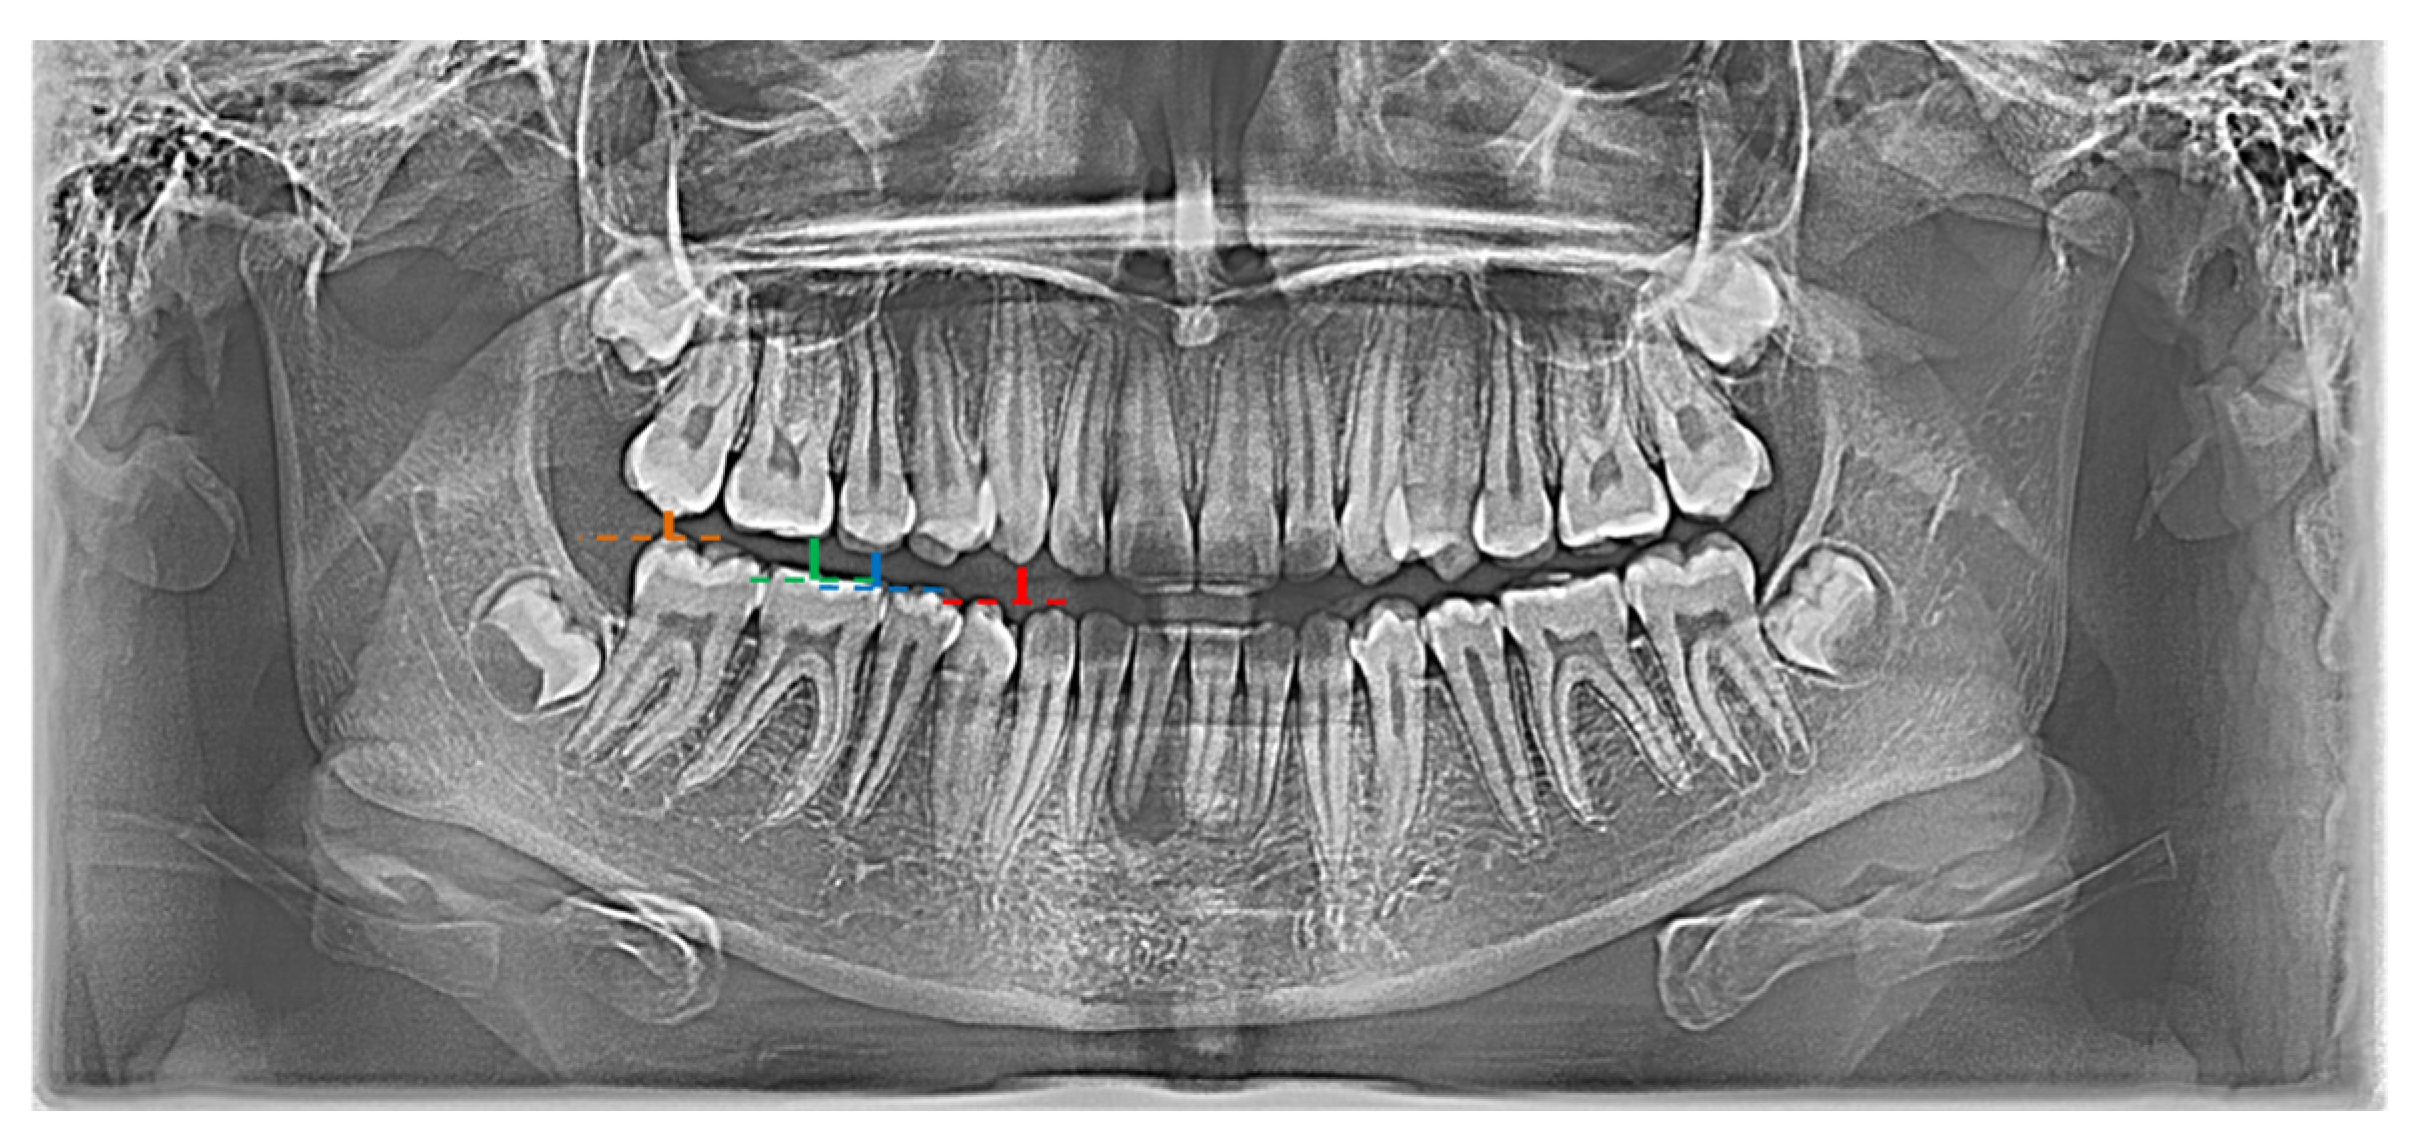

In the conducted research, a set of 21 indicators was used, estimated by Zaborowicz [37]. These indicators were selected to capture most of information about the condition of teeth of children and adolescents. As pantomographic images are not made on a fixed scale, all indicators are calculated as proportions of individual geometric distances, lengths of selected teeth, etc. Please refer to the latest work by Zaborowicz et al. [29], where all the details and descriptions of the indicators can be found. In this work, in order to avoid repetition, only the most important description of the methodology for calculating empirical data is given. Pantomographic photos taken with the Duerr Dental VistaPano S Ceph apparatus were used for the tests. This camera records digital images in the DI-COM 3.0 format, which is supported by the specialized software DBSWIN [38] used for the analysis of 16-bit grayscale, i.e., images dedicated to medicine, including oncology, ophthalmology, cardiology, surgery and dentistry [38]. To collect all indices, i.e., tooth and bone parameters the free, open-source software ImageJ 1.52a [39] was used. Figure 1 and Figure 2 show sample photos and measurements.

Figure 1. Graphical representation of indicator X01 (red |C13C43|; blue |C15C45|).

Figure 2. Graphical representation of selected indicators: X01 (red |C13C43|; blue |C15C45|), X02 (red |C13C43|; green |C16C46|), X03 (red |C13C43|; orange |C17C47|).